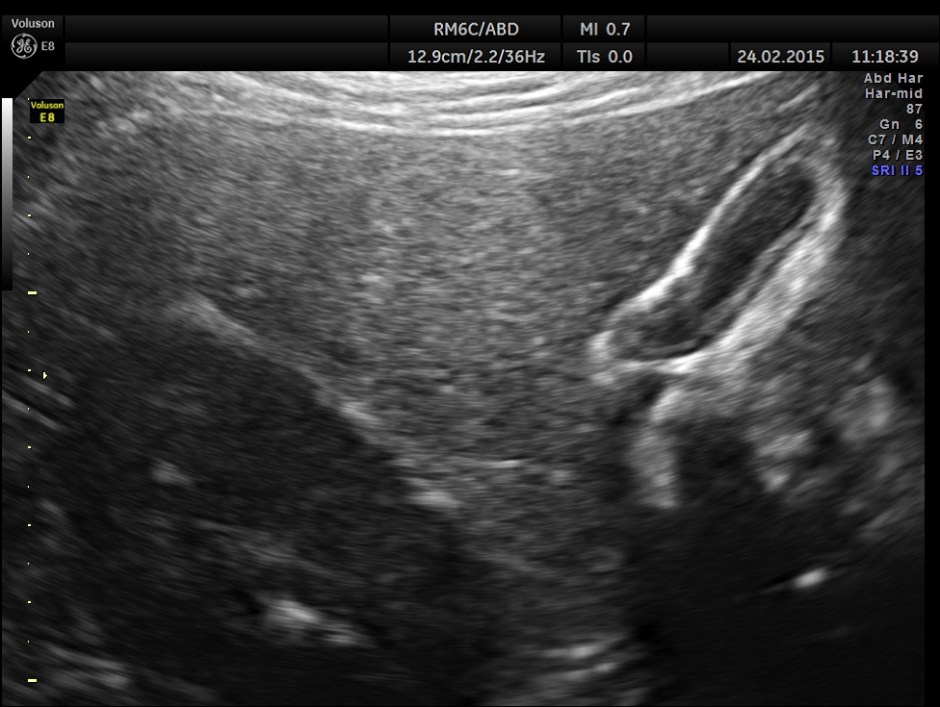

The patient was asked to take a fatty meal and report again and this was seen.The gall bladder has started to be filled up and was showing distension , contrary to what happens in a normal person.